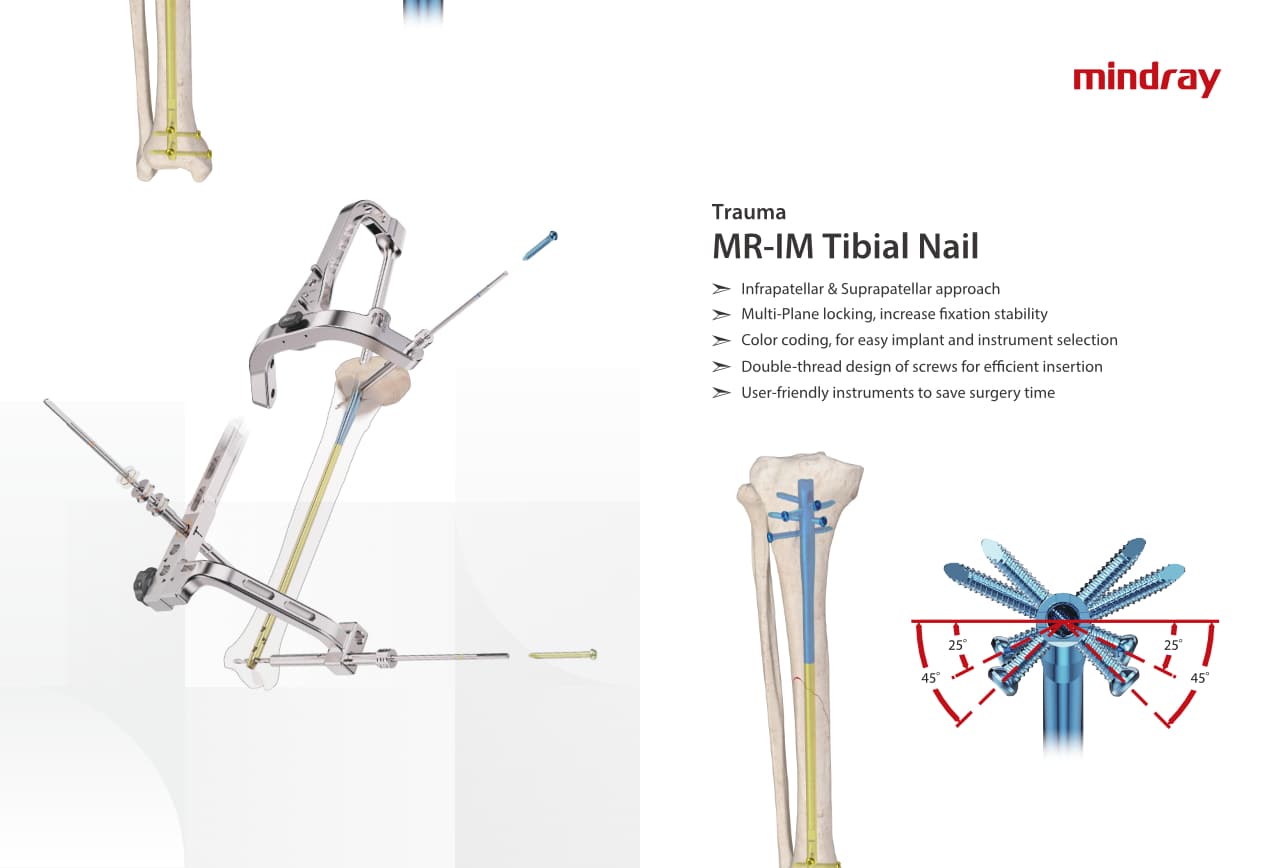

Traumatologie